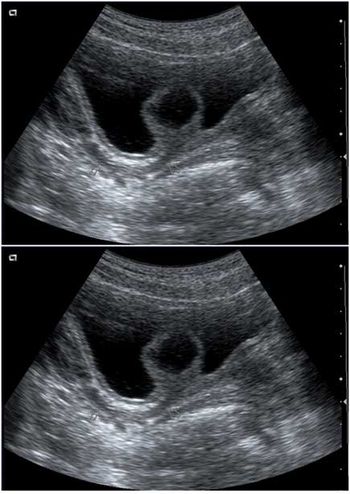

Case History: A 12-year-old girl admitted to our hospital for dysuria. Physical examination was unremarkable. Urianalysis was suggestive of lower urinary tract infection. Urinary ultrasound was indicated.